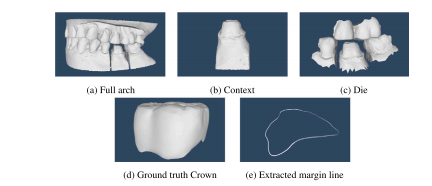

Fig. 3. (a) Dental arch with a prep, (b) generated context, (c) die (prepared tooth),(d) Ground truth crown, (e) extracted margin line.

图3:(a) 带有预备体的牙弓,(b) 生成的背景信息,(c) 代型(预备后的牙齿),(d) 真实的牙冠,(e) 提取出的边缘线。